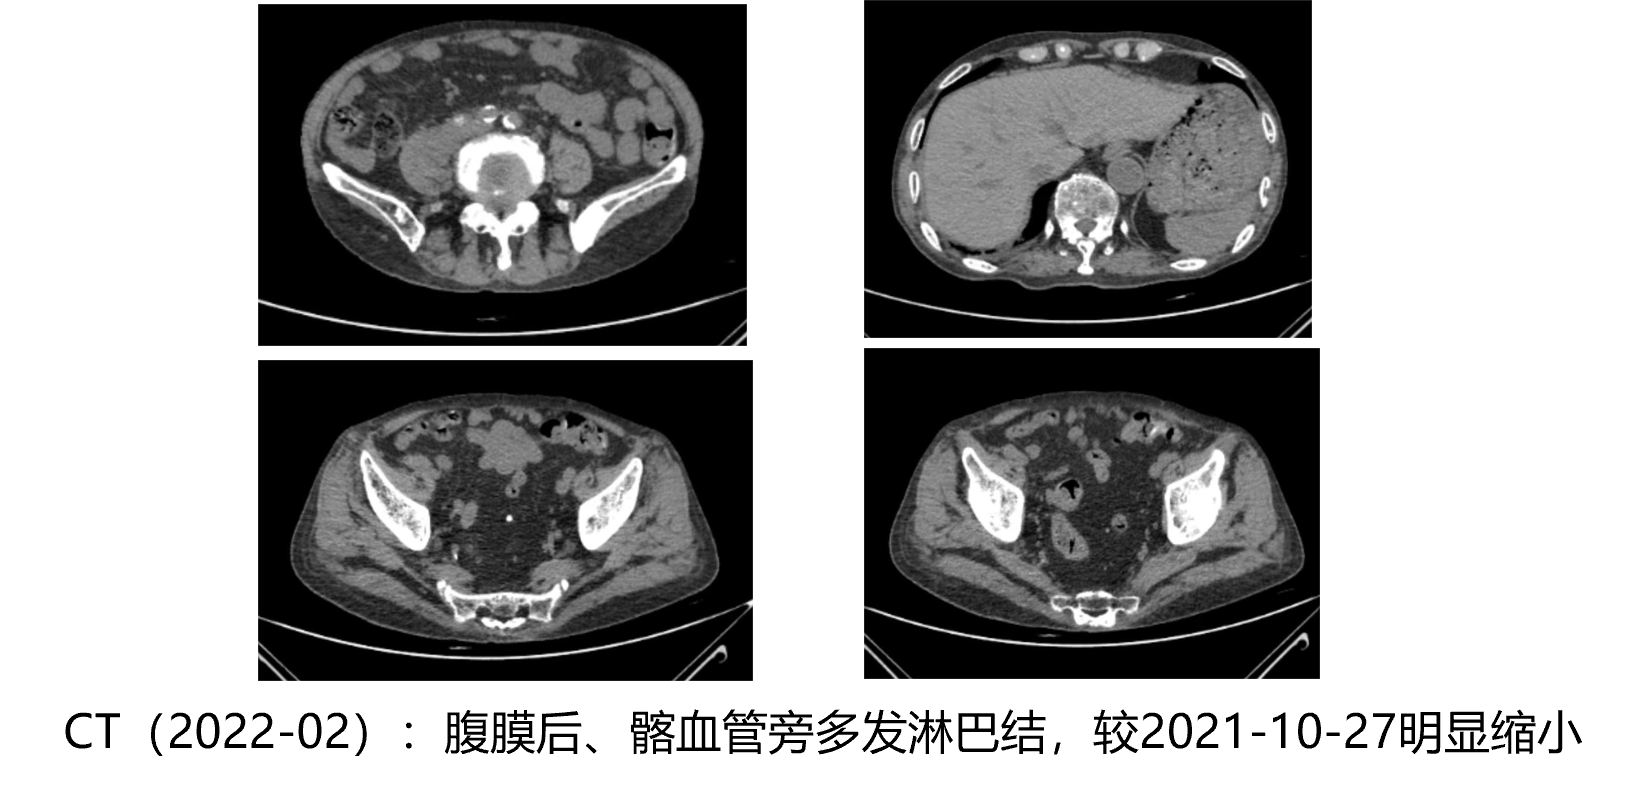

• CT(2020-07):肺部、肝脏等脏器转移未见转移,腹膜后及髂血管旁见少量肿大淋巴结

疗效评估

• 2021年1月-7月: PSA下降至0.008ng/ml,睾酮<20, VAS评分0分,

• 2021年10月: PSA0.28ng/ml,睾酮<20,VAS评分6分,ECOG评分2分

• 2021年10月-2022年4月: PSA下降至0.008ng/ml,睾酮<20,VAS评分2分,ECOG评分1分

影像学评估